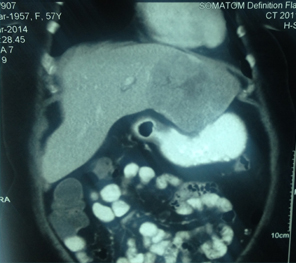

Large HCC in seg 2 & 3

CT Scan showing Lipoidol uptake in segment VIII